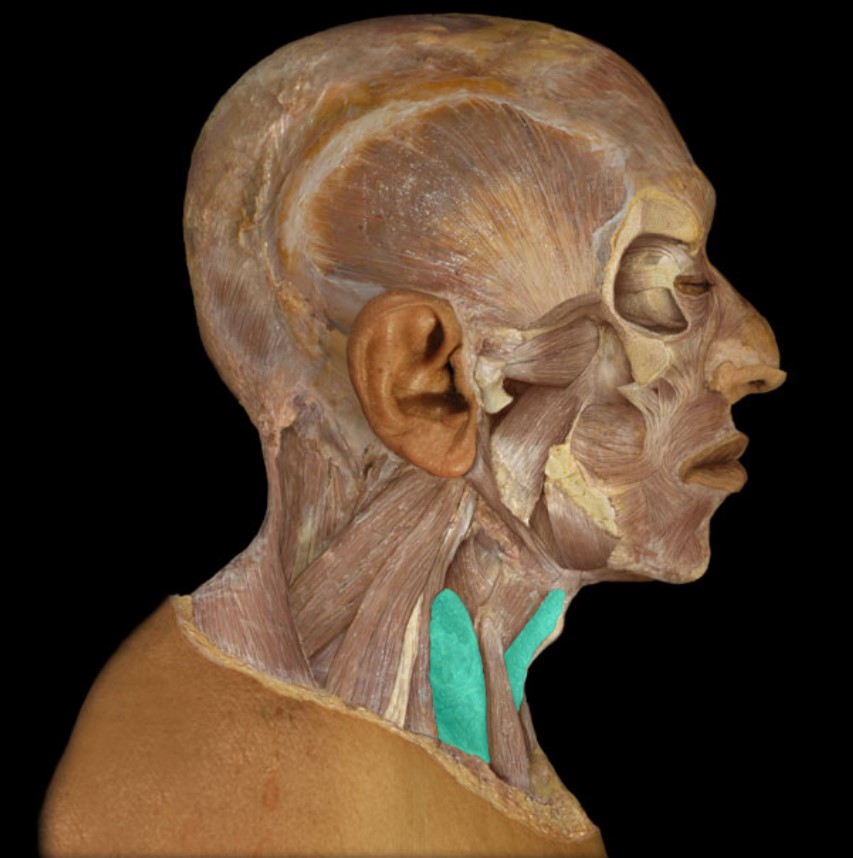

Thyroid Gland

(Donor Only)